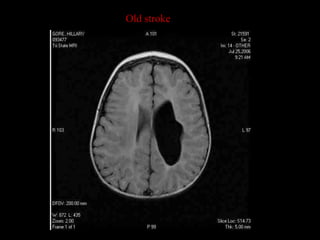

Old stroke